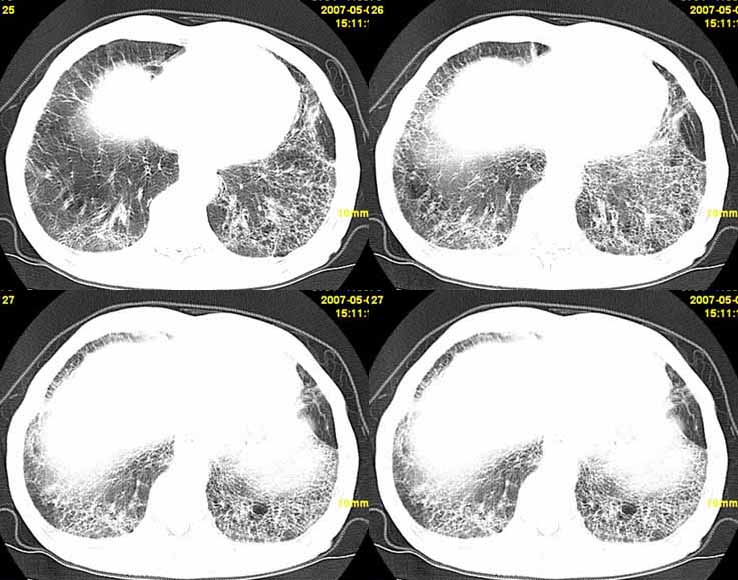

以下是引用小初学者在2007-5-12 11:09:00的发言:[br][br]双肺弥漫性质纤维化(考虑矽肺所致),并发左肺下叶背段周围性肺癌纵隔淋巴转移。

以下是引用zhangzhongshou在2007-5-12 12:09:00的发言:[br]1、左下叶背段周围型肺癌左肺门及纵隔淋巴结转移可能性大。[br]2、弥漫性肺气肿(双侧)。[br]3、双肺间质纤维化。

以下是引用老爱克斯新网客在2007-5-12 12:54:00的发言:[br]1周围型肺癌纵隔肺门淋巴结转移,2肺间质纤维化,